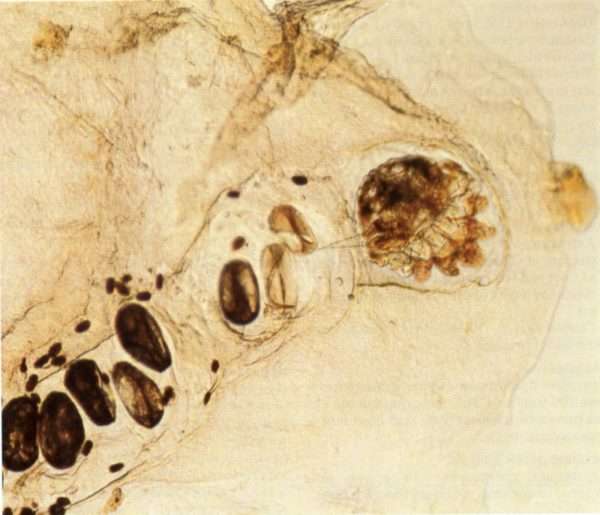

Прежде чем выяснить, как передается чесотка, необходимо знать, откуда она появляется изначально. Как упоминалось выше, заболевание порождает чесоточный клещ (Sarcoptes scabiei). Размеры кожного паразита настолько крохотные, что рассмотреть его можно только под микроскопом.

При попадании на кожу человека самки чесоточного зудня начинают оплодотворяться. После этого они проделывают в эпидермисе отверстие и, продвигаясь вглубь, выгрызают чесоточные ходы, где откладывают яйца. Как правило, одна самка за сутки откладывает по 2-3 яйца, из которых спустя 2 дня появляются личинки, а через пару недель вырастают уже взрослые особи.

Лучше всего чесотка определяется с помощью микроскопического исследования.

Для выявления ходов часто используют йод, который наносят на пораженные участки. В результате таких манипуляций чесоточные ходы окрашиваются в более интенсивный цвет, что свидетельствует о поражении кожи паразитом.

Также используют методику тонких срезов, когда скальпелем или глазными ножницами срезается слой эпидермиса, который впоследствии заливают на 5-8 минут щелочным раствором, а затем исследуют под микроскопом. Благодаря такому способу удается обнаружить не только клещей, но и яйца с личинками.